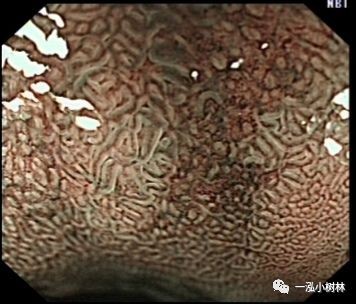

NBI+ME内镜表现:萎缩区域NBI放大可见胃小凹消失或不清晰,树枝状血管显露,黏膜苍白及萎缩边界更明显,多以幽门胃窦部为中心,随着萎缩的加重,胃体黏膜也散见,肠化区域可见胃小凹呈绒毛状,可见到“亮蓝嵴”“白色不透明物质”征。

亮蓝嵴(LBC):位于上皮细胞表面呈脑回样结构脊部的纤细、蓝白色的腺样结构。特征:NBI才能观察到。NBI显示亮蓝色细线样反光,位于上皮细胞边缘。提示肠上皮化生刷状缘。是内镜诊断胃黏膜肠上皮化生的有效标志。

例4

女性,42岁,萎缩性胃炎+肠化+Hp感染